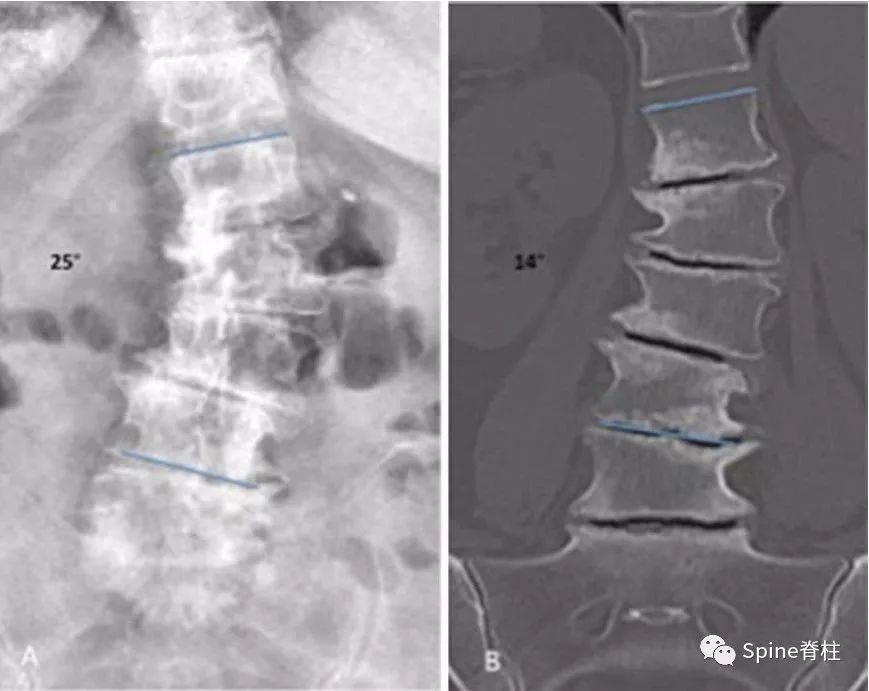

典型的手风琴现象

-

左图为站立位X片,右图为仰卧位CT平扫。站立位负重时的椎间盘与仰卧位(不负重)椎间盘塌陷程度不同,且侧凸角度也不同(分别为25°和14°)。